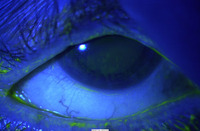

Corneal complication: punctate epithelial erosions that stain with fluorescein

From the collection of Dr E. Akpek